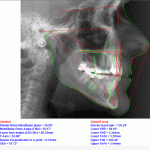

The basic principle of preprogrammed appliances (brackets) is to move teeth on a connecting wire. Each tooth has a specific bracket where a determined torque is milled into the slot. Once a straight wire is attached to the bracket the tooth and its root take up an ideal position. The most commonly used Roth appliance uses the inclinations identified by Dr. Roth on test patients. All other systems follow the same model using slightly different angles.

However, as all these systems reference a position copied from Roth’s model without taking into consideration the actual position of the patient’s tooth and the planned movement, all patients consequently get the same appliance regardless of their needs. As a consequence, in order to correct positions inadequate forces sometimes need to be applied or simply the case remains under-corrected or gets corrected surgically.

In Deutsche ZK clinic we administer an intelligent digital system which considers mainly the starting position. The IP®- appliance (USA) uses Roth’s values as a basis without limiting itself to 28 brackets but instead having 250 different appliances.

Given the fact that a tooth moves within its bone, the foreseen movement of the root as well as its position is quantified digitally and computer-supported in order to determine a specific appliance so that all problems get corrected from the very beginning. This way a faster and safer correction can be administered where applied forces are light and consequently the result is more consistent.